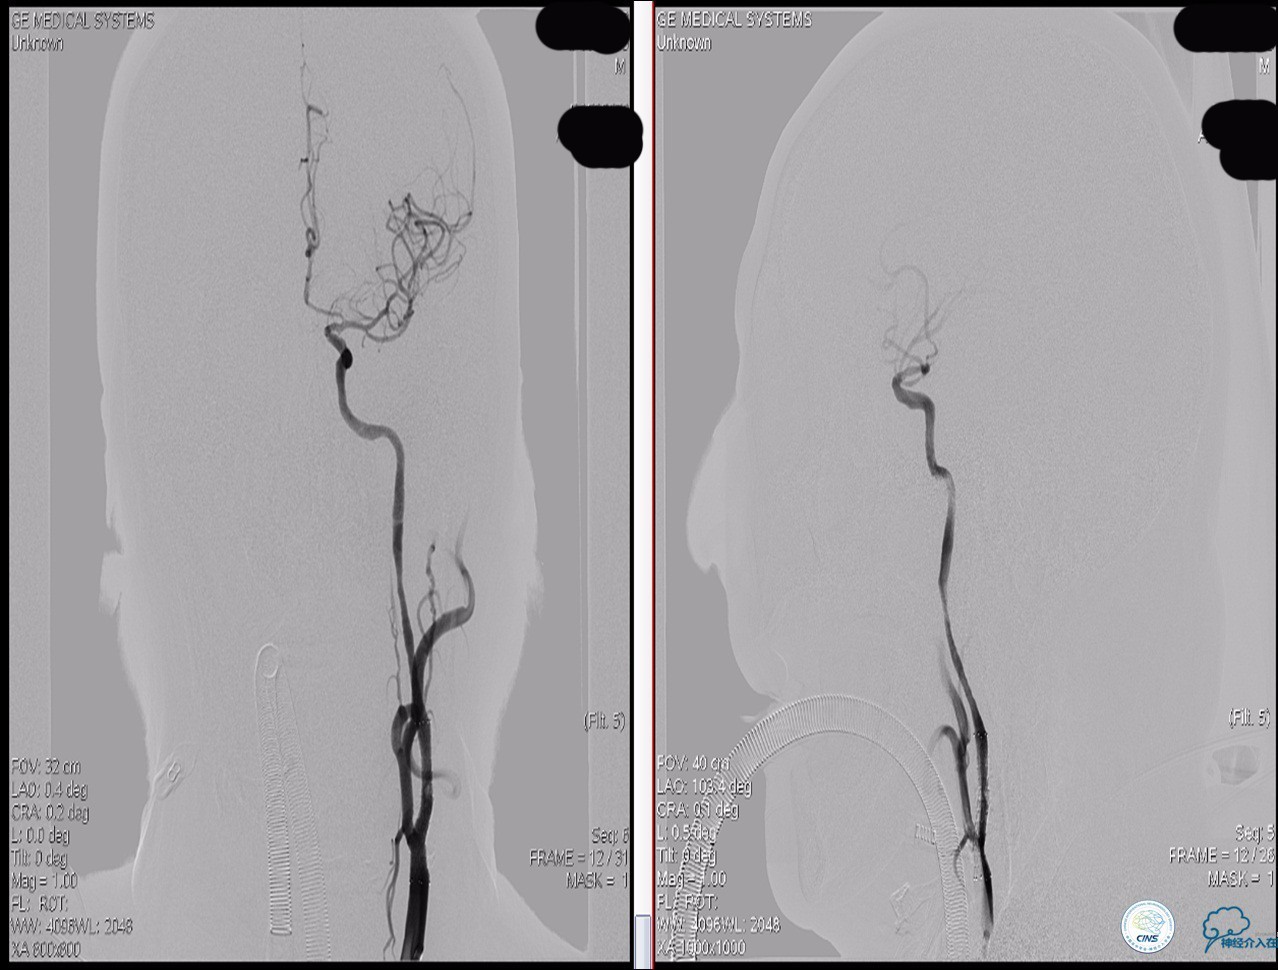

颈动脉次全闭塞 术前评估

》头颅灌注+DSA!

头颅灌注: 注意两侧CBF CBV的对比。

DSA:注意侧支代偿。